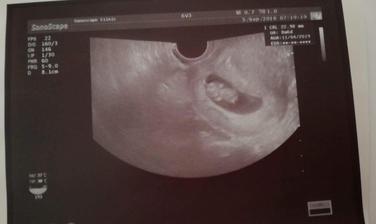

autor@hekina1232 v 11 tyzdni som

autor@hekina1232 ja ked som sla k Dr bola som v 6-tyzdni....meskala mi MS 7-dni

Mne mešká u cca 12 a iba taká malá guľka za 2tyzdne mám ísť zase